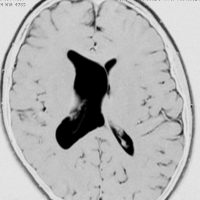

シルビウス裂くも膜のう胞,中頭蓋窩くも膜のう胞

最も多いタイプで50%くらいです。7歳の子に偶然発見された右シルビウス裂のくも膜のう胞です。大きいのですがこの程度では治療の必要はありません。シルビウス裂のくも膜のう胞は最も多いものです。